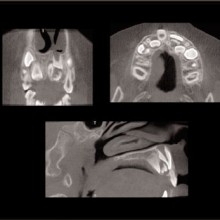

TEMPOROMANDIBULAR JOINT EVALUATION: It is not uncommon for individuals seeking dental treatment to have TMJ conditions that may alter the size, form, quality, and spatial relationships of the osseous joint components. When these conditions occur during development, they may alter the growth of the ipsilateral half of the mandible with compensations in the maxilla, tooth position, occlusion, and cranial base. Severe TMJ conditions may also alter the facial growth pattern. Skeletal and dental changes occur in the vertical, horizontal and transverse directions thus making them difficult to accurately characterize with conventional two-dimensional imaging, such as cephalometric, tomographic, and panoramic projections. CBCT creates the opportunity to visualize and quantify the local and regional effects associated with the TMJ abnormalities. CBCT allows, for the first time, to visualize the TMJs and at the same time, assess the maxillomandibular spatial relationships and occlusion.

IMPACTIONS: Imaging can contribute greatly to localizing impacted teeth, identifying associated pathology, assist planning surgical access, and assist with designing the traction mechanics for moving the impacted tooth into the dental arch and occlusion (Figures 9, 10).

The anatomy sets some of the boundary conditions for tooth position. The identification and visualization of these boundary conditions can be performed by applying volumetric CT during initial workup. There are clinical instances when tooth movement is prevented or diminished because of anatomic boundaries, such as cortical margins, adjacent teeth, and dense bone. In addition, expansion of the dental arch form or tooth torque may be limited or confined by the labial and buccal cortical margins of the alveolar bone. These boundaries are difficult to visualize without the aid of cross sectional or three-dimensional imaging techniques (Figure 9).

With the traditional two-dimensional dental-imaging series some areas of anatomy are poorly visualized. These three-dimensional scans can give valuable information about other areas of the dentition such as the position of the upper incisor roots relative to the lingual cortical border of the palate to plan retraction, the amount of bone available in the posterior maxilla available for distalization, the amount of bone lateral to the maxillary buccal segments available for dental rather than skeletal expansion, airway information on the pharynx and nasal passages, upper root proximity to the maxillary sinus, the three-dimensional extent of an atrophied alveolar ridge, or the position of the lower incisor roots in bone. These scans also allow three-dimensional visualization of bony defects and supernumerary teeth in patients with cleft lip and/or palate. Additionally, axially corrected tomograms of the temporomandibular joints can be obtained from the same scan. The ability to visualize an axially corrected view of the temporomandibular joints with the teeth in occlusion on the same reconstructed section is one significant advantage of the volume scan. Therefore, there is substantial “value-added” imaging benefits to these scans for complicated orthodontic patients.